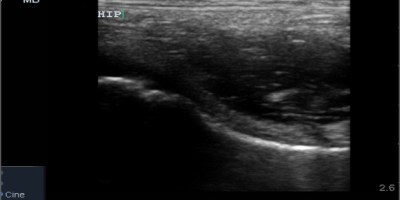

Make the POCUS diagnosis, sono of the week, Sono Stuff